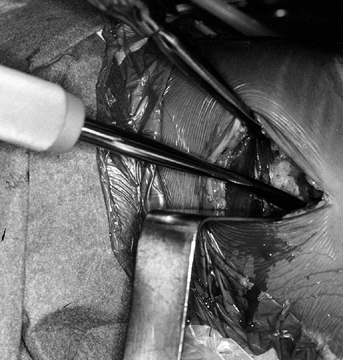

Make the incision (Fig. 89.4)

from the tip of the patella to 2 cm below the tibial tubercle, slightly

medial to the midline, so the tibial tunnel can be placed through the

incision. A smaller, more cosmetic incision can be used if adequate

skin mobility is present. Carry the incision

down sharply to the peritenon and then incise it with a #15 scalpel blade.

Figure 89.4.

View of a right knee. Make the incision slightly medial to the midline,

from the distal tip of the patella to 2 cm below the tibial tubercle,

approximately 8 cm in length. Placement of superomedial, inferomedial,

and inferolateral portals is depicted as well. Should the graft

harvesting occur before arthroscopy, place the inferomedial and

inferolateral portals through the graft harvest incision. -